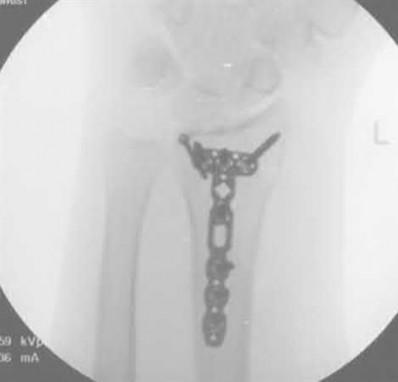

A 23-year-old female is an unrestrained driver in a motor vehicle collision, sustaining the injury shown in Figure A. She subsequently undergoes reduction and percutaneous bilateral iliosacral screw placement. Which of the following is the most likely neurologic complication associated with percutaneous iliosacral screw insertion?

Figure A shows an unstable bilateral pelvic ring injury. Percutaneous posterior iliosacral screw fixation places the L5 nerve root at risk as it courses across the sacral ala. Injury to the L5 nerve root would typically result in weakness in great toe extension and sensory changes on the dorsum of the foot. It is important to notice that L5 often partially innervates tibialis anterior along with L4, so weakness to ankle dorsiflexion may be present as well. Illustration A shows the post-operative films with bilateral iliosacral screws.